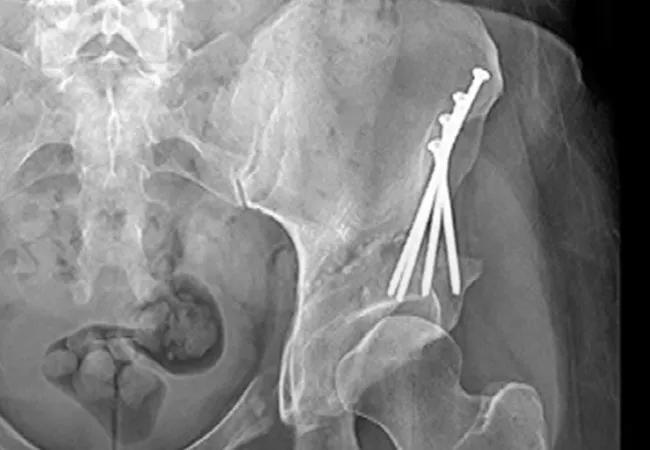

A 37-year-old female presented to Cleveland Clinic’s Department of Orthopaedic Surgery with symptomatic bilateral hip pain. Her symptoms had progressed since an injury to her right hip six months previously. Computed tomography (CT) imaging showed underlying bilateral hip acetabular dysplasia, in addition to severe arthritis of the right hip and preserved cartilage of the left hip.

For this reason, he explains, he elected to perform arthroplasty of her right hip and, at a future date, would perform a periacetabular osteotomy of the left hip. Periacetabular osteotomy involves rotating the acetabulum, optimizing the surface for the femoral head – a procedure that can delay or prevent the progression of osteoarthritis.1

Three months after the first procedure, Dr. Kamath performed the periacetabular osteotomy on the left hip through a Smith-Petersen/direct anterior approach. The patient did well with high functional activity at final follow-up.